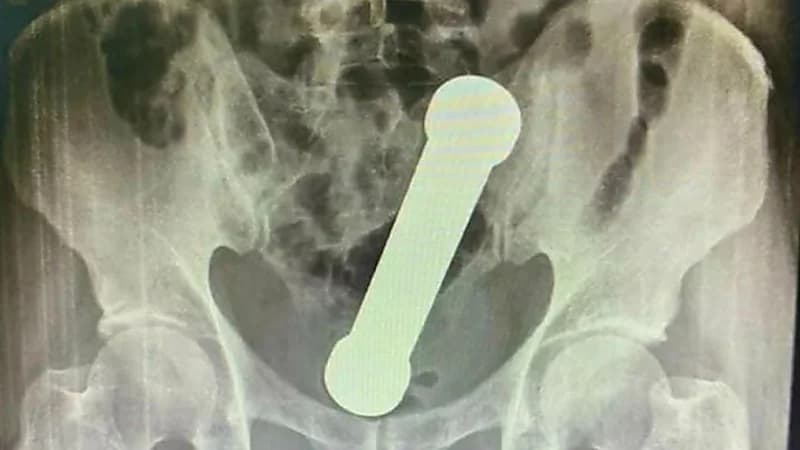

كشفت مستشفى ماناوس بالبرازيل عن إنقاذ حياة مُسن برازيلي دخل في جسده دمبل بوزن 2 كيلوجرام في حادثة غريبة لم تشهدها من قبل .

وبعد أن اجري المسعفين تصوير باطنه بالأشعة السينية للرجل الذي يبلغ من العمر54 عاماً قرروا ضرورة إزالة الدمبل بأيديهم.